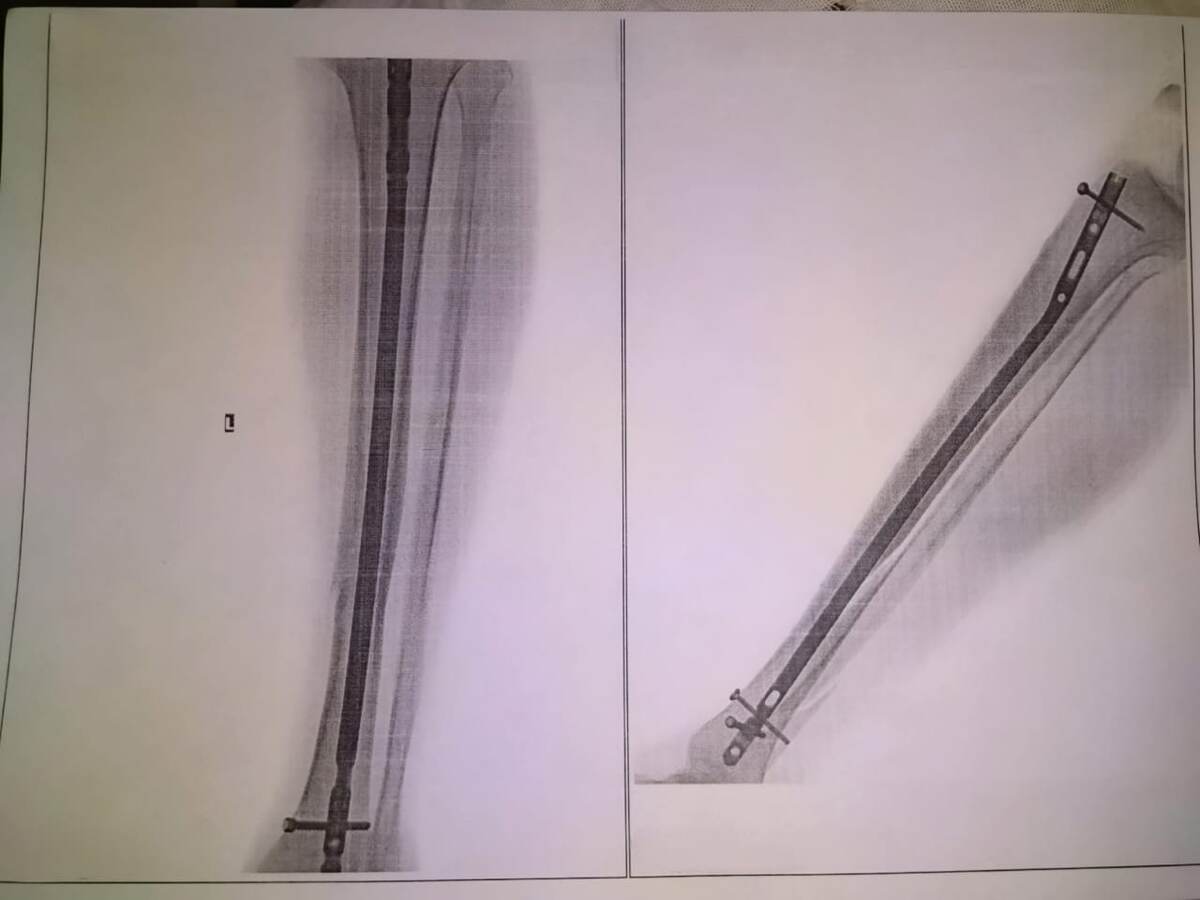

В операционной мне сделали спинальную анестезию (укол в спинной мозг), после которой ниже укола я уже ничего не чувствовал, но в остальном находился в сознании. На левую руку мне поставили капельницу с физраствором, к правой подключили мониторы. Операция заняла минут 20-30 по ощущениям. Мне сделали короткий разрез под коленкой, ввели металлический штифт внутрь мозгового канала большеберцовой кости и прикрутили к этому штифту шурупами верхнюю и нижнюю части сломанной кости. Наложили несколько швов, перевязали и привезли обратно в палату. С малой берцовой костью ничего не делали. Примерно часам к 6 вечера отошел наркоз.

Контрольный рентген моей ноги на следующий день после операции